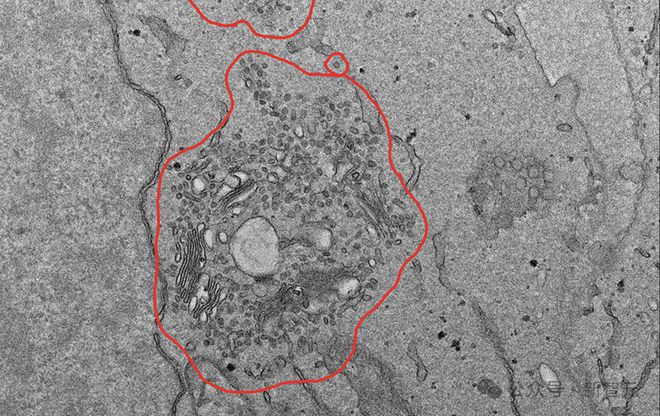

如下,是一个典型的 VCT 问题,描述了一个场景,并且只能通过视觉信息解决,最后从提供的 7 个答案陈述中确定哪些是正确的。